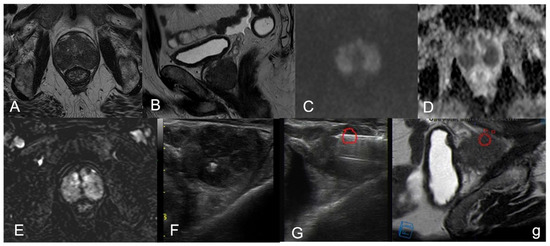

| 1 | PZpm mid-left; TZa mid-base right | 2-cm hypointense PZ nodule; 1.5-cm marker hypointense irregular TZ lesion | Isointense nodule; Slightly hyperintense | Marked low ADC value; Low ADC value | Peripheral rim enhancement and avascular core; Inhomogeneous, early and prolonged hyperenhancement | 4; 5 |

| 2 | PZpl mid-left | 2.5-cm hypointense nodule, capsular bulging | Hyperintense | Low ADC value | Thick peripheral rim enhancement, avascular core | 4 |

| 6 | PZ diffuse (index lesion PZpm mid-base left; TZa base right | Confluent pseudonodular hypointense areas, capsular bulging; 2-cm marked hypointense irregular TZ lesion | Marked hyperintense; hyperintense | Marked low ADC value; Marked low ADC value | Peripheral rim enhancement and avascular core in the index lesion; inhomogeneous, intense and prolonged enhancement | 5; 5 |

| 8 | PZpm mid-base left | Markedly hypointense nodule, focal capsular bulging | Marked hyperintense | Marked low ADC value | Peripheral rim enhancement, avascular core | 5 |